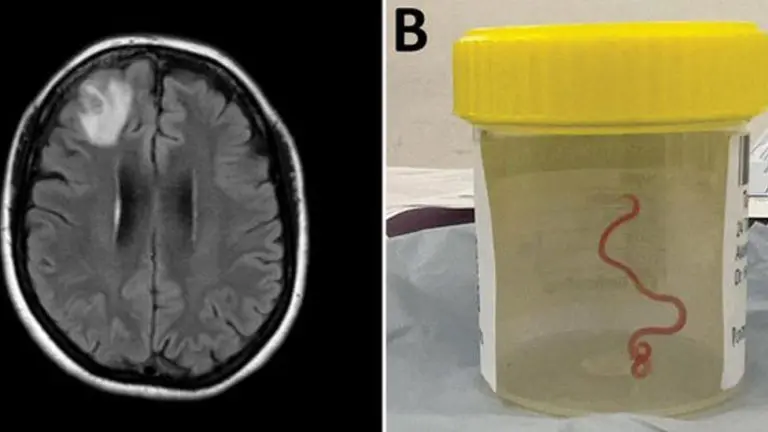

Ljekari pronašli živog crva u mozgu žene tokom operacije